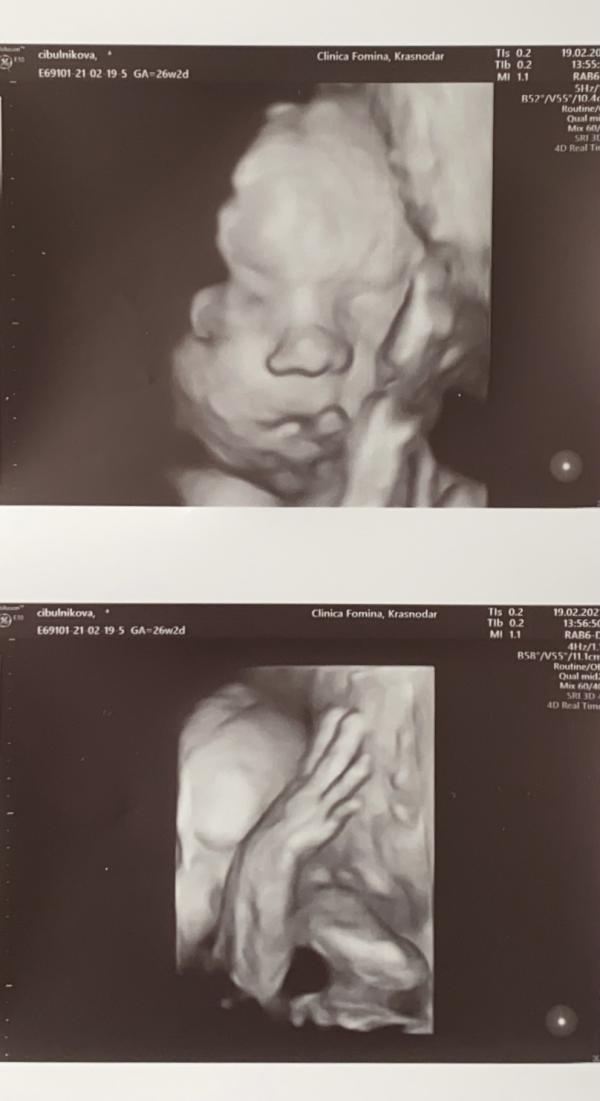

Какая прелесть 😊😊😊тоже ходила недавно в Фомина по акции, но мой так удачно не повернулся😐жду следующего узи

Спасибо) да врач тоже долго пыталась поймать удачный момент , но малышка постоянно закрывалась рукой ( ну ничего , хоть так получилось ))может у вас чуть в подрастёт и уже удобнее будет поймать ракурс

@natali_tss может, но он лежал головкой вниз, и ручками закрывал лицо, Клипа и так старалась и так, но он маленький партизан🤰😂